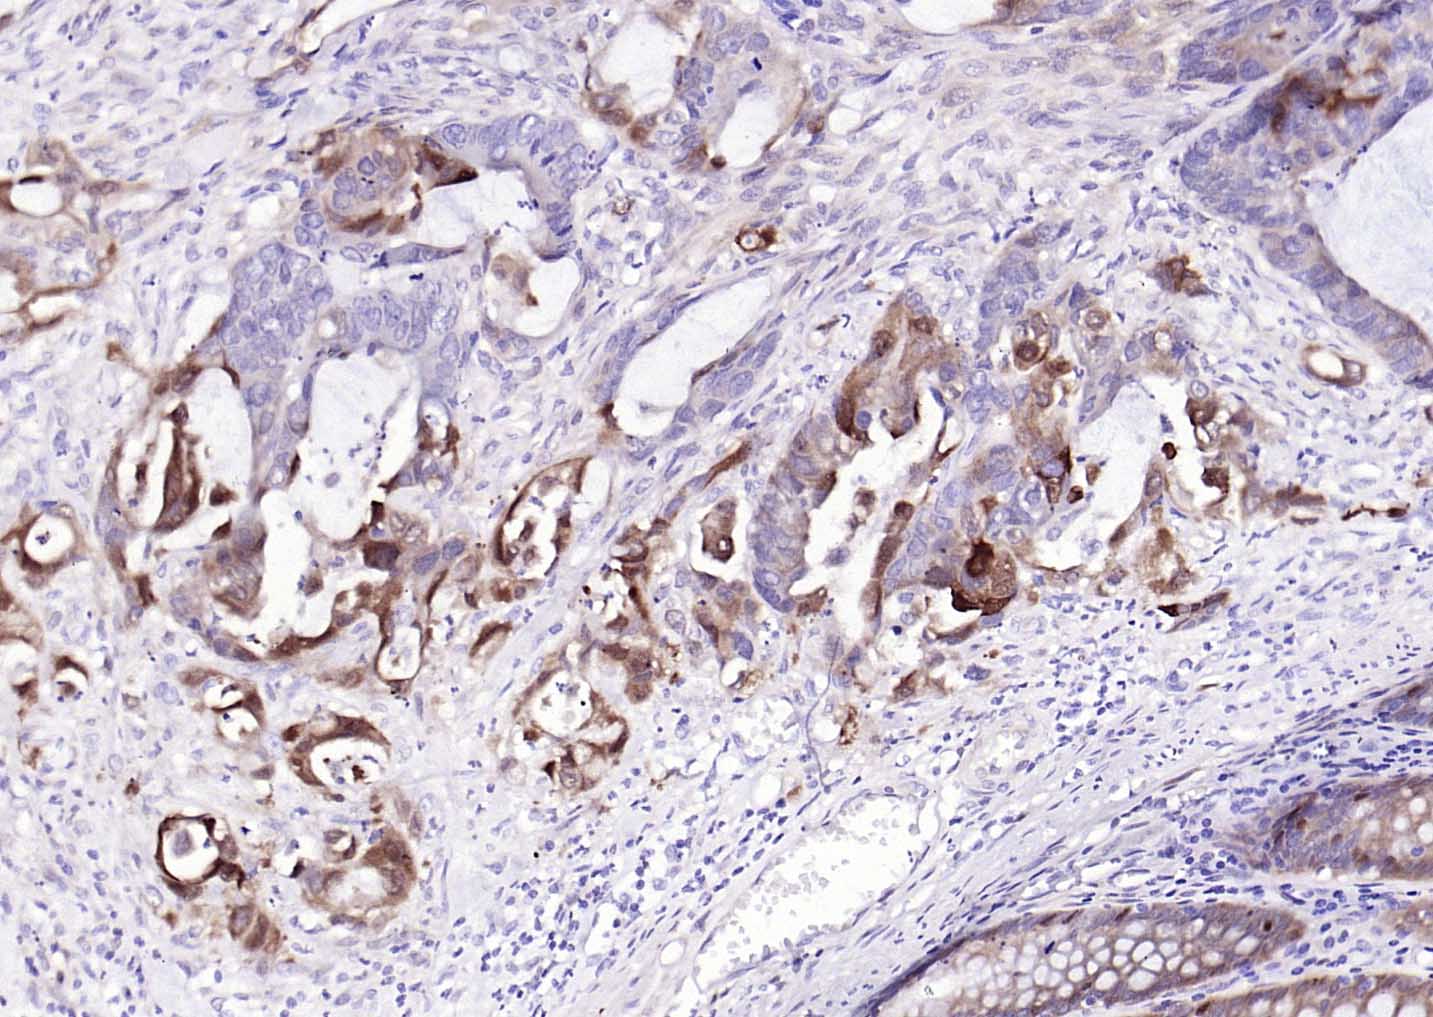

| 产品应用 | WB=1:500-2000, IHC-P=1:50-200, IHC-F=1:50-200, IF=1:100-500, Flow-Cyt=1:50-200 Not yet tested in other applications. |

| {IHC-P} | {1:50-200} |